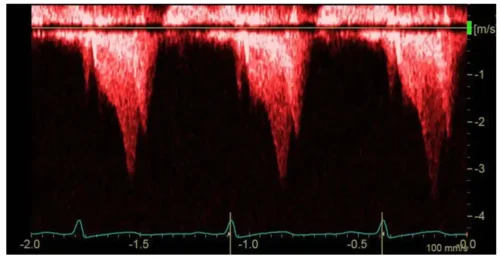

به طیف گسترده فرکانسها/سرعتها توجه کنید که باعث پهنشدن طیف فرکانسی داپلر CW میشود. در مقایسه با داپلر موج پالسی (PW)، نمایش داپلر CW معمولاً **پهنشدگی طیفی** بیشتری دارد و **پنجره پروفایل داپلر پرتر** دیده میشود. این موضوع نشاندهنده وجود **دامنه وسیعی از سرعتها** در حجم نمونه بزرگ داپلر CW است.

(A) در نمای چهارحفرهای اپیکال با تمرکز بر RV، جت نارسایی دریچه تریکوسپید (TR) با استفاده از داپلر رنگی شناسایی میشود. دقت میشود که جهت جت TR تا حد امکان موازی با پرتو اولتراسوند باشد.

(B) داپلر موج پیوسته (CW) روی ونا کونتراکای جت (محل تنگترین بخش جت) TR قرار داده میشود و تنظیمات گین، برد (range) و سرعت جاروب (sweep speed) بهینه میگردد.

(C) سپس حداکثر سرعت اندازهگیری میشود؛ این مقدار را میتوان با استفاده از پروب بدون تصویر (نیز بررسی مجدد کرد.

(D) میانگین سرعت TR را میتوان با ترسیم پاکت داپلر و محاسبه انتگرال سرعت–زمان (VTI) برآورد کرد.